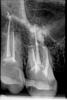

Медэстетка Опубликовано 13 апреля, 2011 Автор Поделиться Опубликовано 13 апреля, 2011 Сегодня закончила лечение.Применила 30% лимонку,прошла ещё раз ультразвуком.Не судите строго,но всё же не рискнула работать гипохлором,в качестве альтернативы применила спирт.Будь уже как будет.Размещаю обещанный снимок.Пломбировка сделана термафилами.То ,что за верхушками пузыриться-это кальций,вроде старалась ввести чуть,но получилось как есть. Ссылка на комментарий

zybnaya feya Опубликовано 13 апреля, 2011 Поделиться Опубликовано 13 апреля, 2011 Пломбировка сделана термафилами.То ,что за верхушками пузыриться-это кальций,вроде старалась ввести чуть,но получилось как есть.Обтурация нормуль. А почему хлоргексидином не мыли? Ссылка на комментарий

д-р Вит Опубликовано 13 апреля, 2011 Поделиться Опубликовано 13 апреля, 2011 (изменено) Сегодня закончила лечение.Применила 30% лимонку,прошла ещё раз ультразвуком.Не судите строго,но всё же не рискнула работать гипохлором,в качестве альтернативы применила спирт.Будь уже как будет.Размещаю обещанный снимок.Пломбировка сделана термафилами.То ,что за верхушками пузыриться-это кальций,вроде старалась ввести чуть,но получилось как есть.пломбировка понравилась,все будет нормально,молодец зы как удалось высушить каналы,не подтекало после спирта? Изменено 13 апреля, 2011 пользователем д-р Вит Ссылка на комментарий

Ico Опубликовано 13 апреля, 2011 Поделиться Опубликовано 13 апреля, 2011 Сегодня закончила лечение.Применила 30% лимонку,прошла ещё раз ультразвуком.Не судите строго,но всё же не рискнула работать гипохлором,в качестве альтернативы применила спирт.Будь уже как будет.Размещаю обещанный снимок.Пломбировка сделана термафилами.То ,что за верхушками пузыриться-это кальций,вроде старалась ввести чуть,но получилось как есть.http://s014.radikal.ru/i327/1104/e8/b360b8913cf7.jpg Помоему канальчик недобит Ссылка на комментарий

Медэстетка Опубликовано 13 апреля, 2011 Автор Поделиться Опубликовано 13 апреля, 2011 Обтурация нормуль. А почему хлоргексидином не мыли?Такая мысль возникла.Но потом вспомнила,как на одной из учёб(москвичи)упоминали про спирт.Приводили протокол ирригации,где он одним из пунктов.Но толькл 70 гр.-он разрушает,а 95-обволакивает.Да и хлоргексидин в кабинете оказался просроченным... пломбировка понравилась,все будет нормально,молодец зы как удалось высушить каналы,не подтекало после спирта?Подтекало через раз,ну самую малость.Хорошо погоняла гут. штифтом спирт в каналах,потом долго сушила,оставляла пины в каналах,не вынимая-обтурировала по очереди. А как она себя чувствует?Отделяемое из носа прекратилось?Ну она мне очень даже понравилась, настрой был доброжелательный.Только всё время подозрительно принюхивалась,а не достаю ли я хлорку.Я поделилась с ней знаниями анатомии,касаемых строения её гайм.пазухи.Из носа,с её слов текло два дня.Ну а в день приёма было сухо.Антибмотик продолжает пить. http://s014.radikal.ru/i327/1104/e8/b360b8913cf7.jpg Помоему канальчик недобит Это боковое ответвление нёбного,и открылось скорее всего после лимонки и уз. Когда каналы искала и разрабатывала-им и не пахло.А тут на тебе!Там скорее всего только силлер. Ссылка на комментарий

ger_berra Опубликовано 13 апреля, 2011 Поделиться Опубликовано 13 апреля, 2011 Это боковое ответвление нёбного,и открылось скорее всего после лимонки и уз. Когда каналы искала и разрабатывала-им и не пахло.А тут на тебе!Там скорее всего только силлер.Это нёбный такой короткий? Ссылка на комментарий